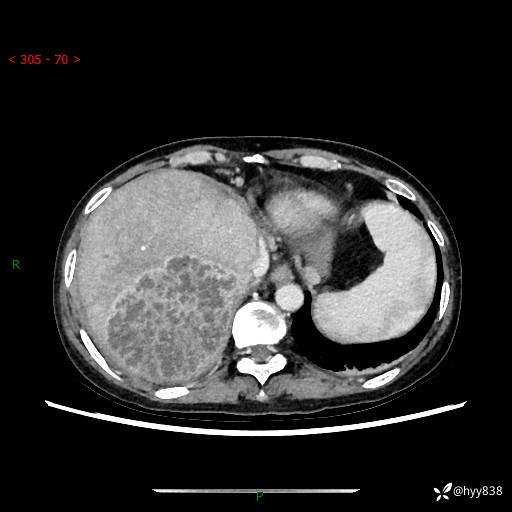

病例老年女性,发热来诊。如此“蜂窝煤”,治疗很棘手---结果公布~

性别:女

年龄:53岁

简要病史:发热(门诊急诊患者)

上腹部CT平扫